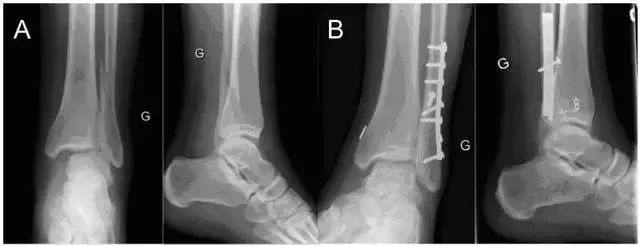

图 2  使用带袢纽扣钢板固定下胫腓联合损伤示意图

A 一例典型的 Weber C 型骨折;B 开放复位并使用带袢纽扣钢板固定术后踝关节正侧位片(图片来自文献 [7])